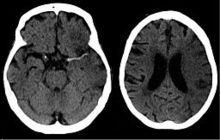

CT scan of the brain showing a prior right-sided ischemic stroke from blockage of an artery. Changes on a CT may not be visible early on.[1]

A CT showing early signs of a middle cerebral artery stroke with loss of definition of the gyri and grey white boundary

Dens media sign in a patient with middle cerebral artery infarction shown on the left. Right image after 7 hours.